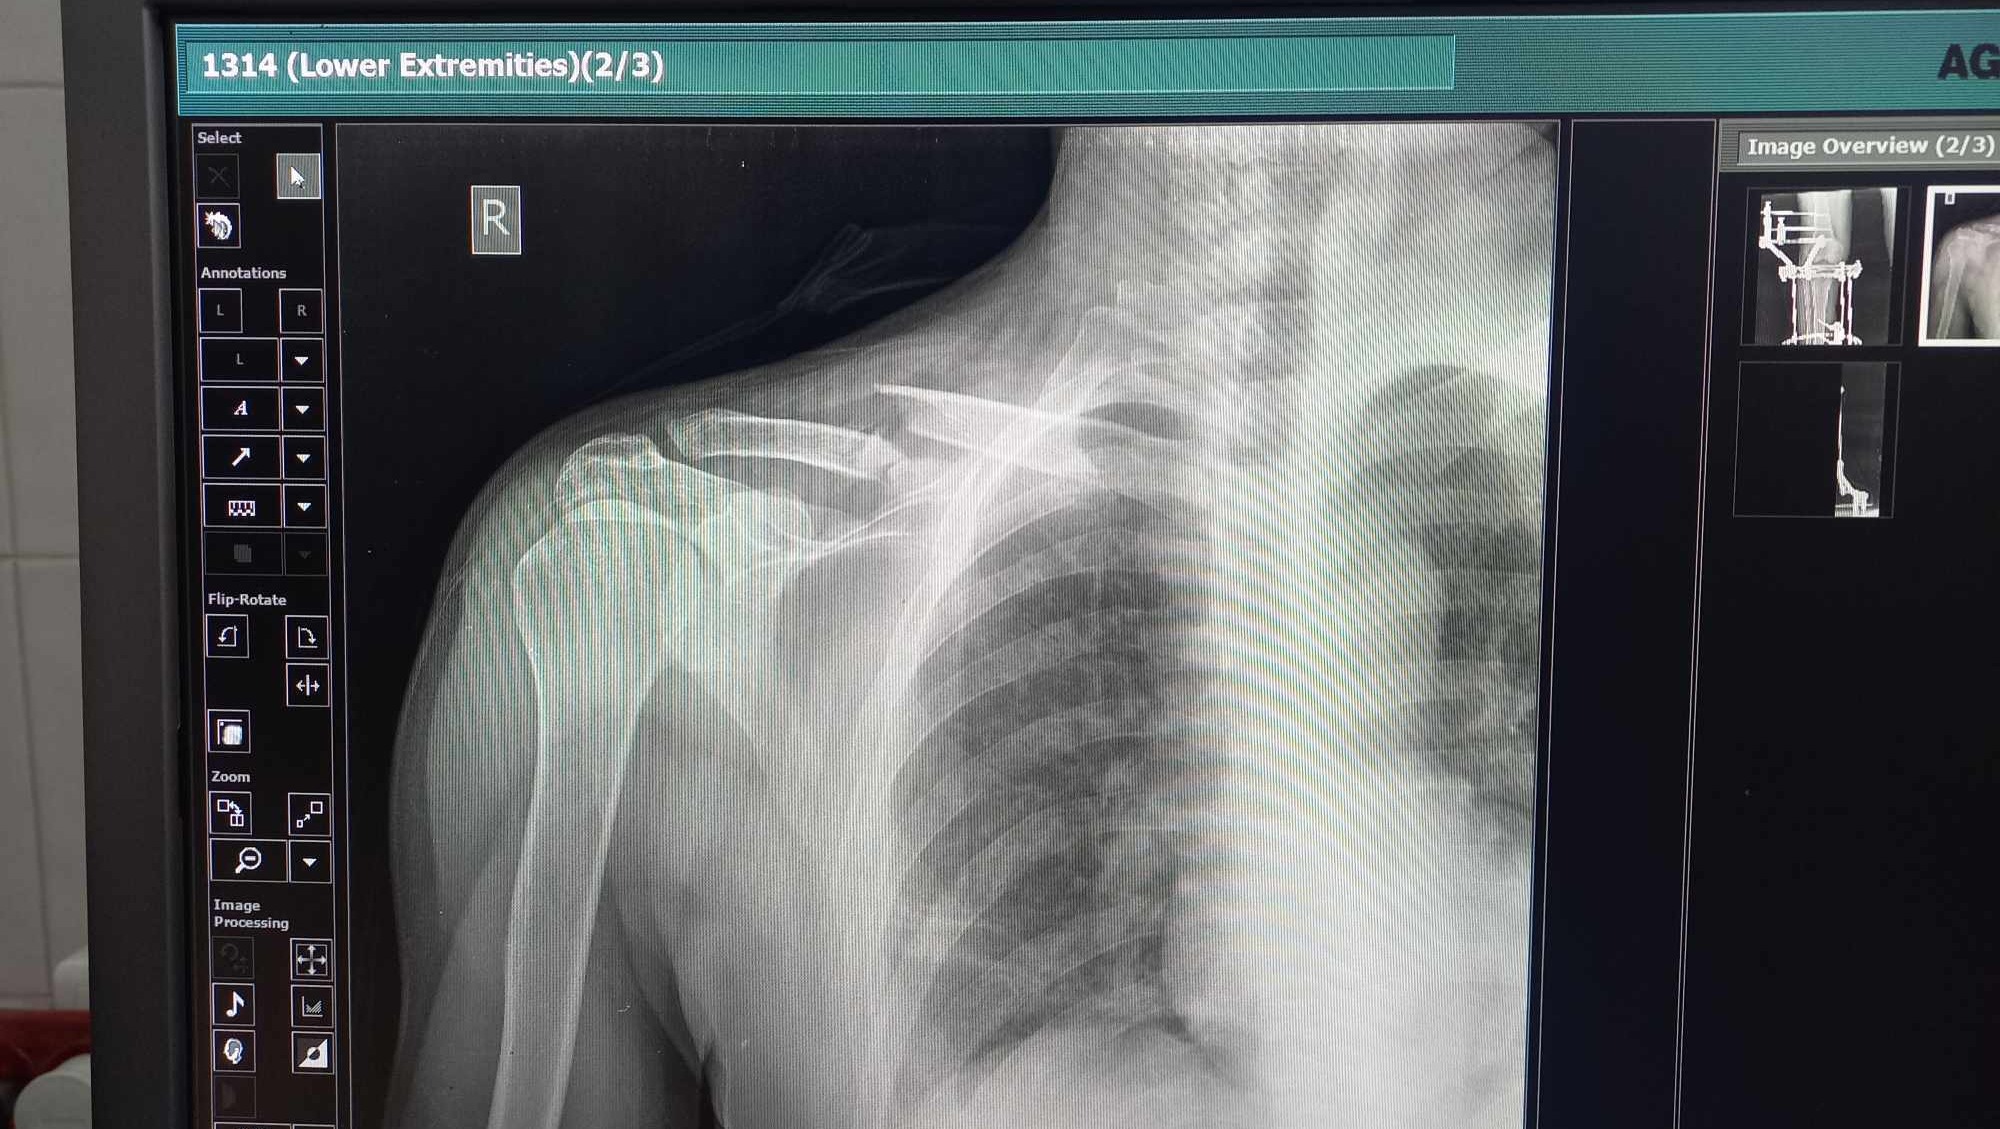

In March of last year, our world turned upside down when my dad had a bad motorcycle accident. The crash broke his knee and shoulder bones really badly, and he needed surgery with a special metal plate to fix them. He had one surgery, but it wasn't enough to make him feel completely better again. And on top of all that, his shoulder was broken again during the war. His health plummeted, and he found himself right back where he started.